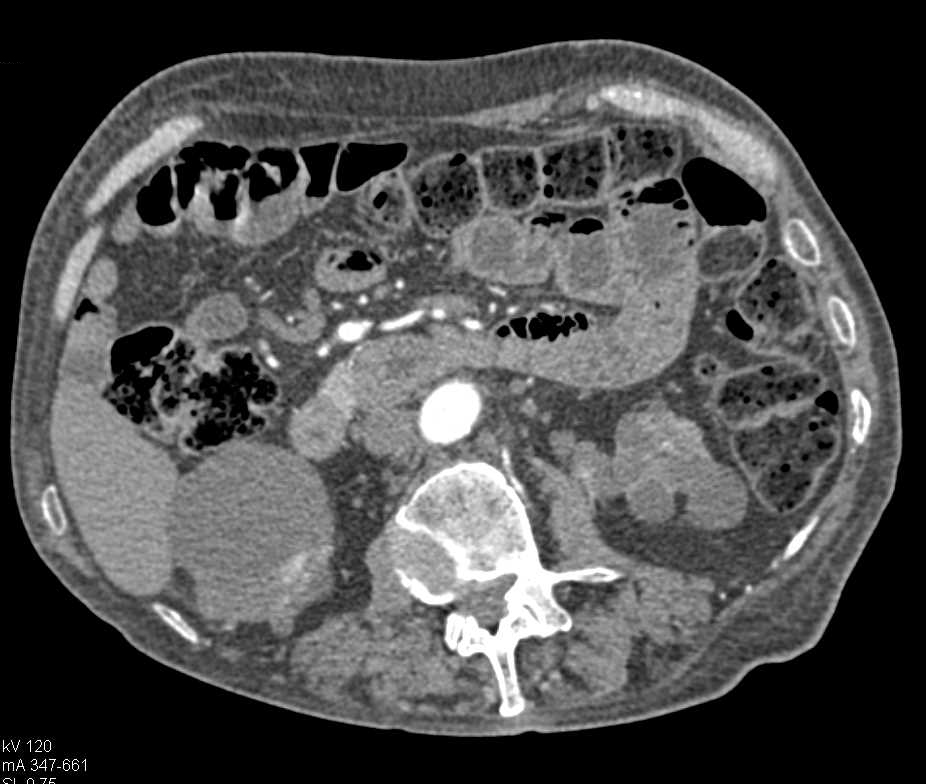

Transitional Cell Carcinoma Left Kidney